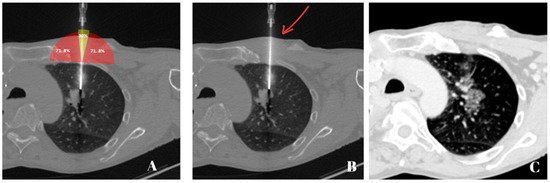

2. Materials and Methods

2.4. Biopsy Protocol

2.5. Measurement Yield